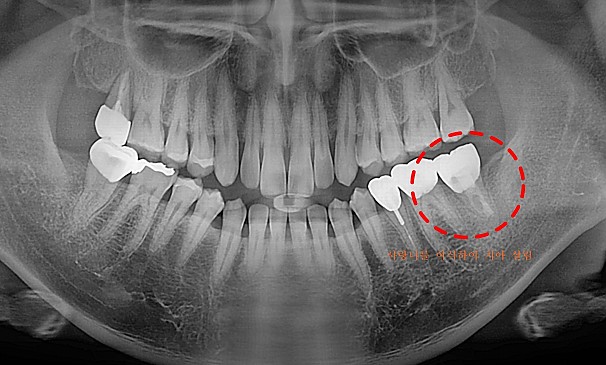

자가치아이식술란?

도저히 살릴 수 없는 치아를 뽑고 그 자리에 자신의 사랑니를 이식하는 치료방법입니다.

기능이 없는 사랑니를 이동하여 이식함으로써 내 자연치아를 사용할 수 있습니다.

모OO님 전후사진 | 치료 기간 : 2주

치료 전

치료 후